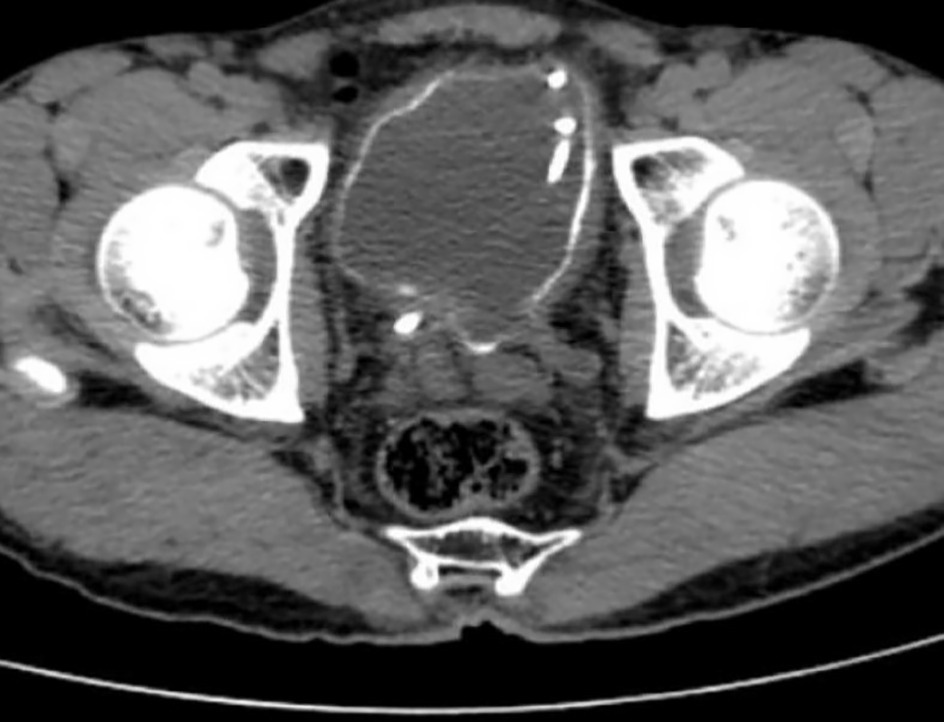

Les symptômes persistant, un scanner pelvien, quelques jours après, révèle une importante calcification de la paroi vésicale (figure).

L’ASP peut objectiver des calcifications de la paroi vésicale, et de l’uretère. À l’échographie ou au scanner pelvien : calcifications, pseudopolypes vésicaux, résidu post-mictionnel, mais aussi urétéro-hydronéphroses, dilatations pyélocalicielles avec image en boule.